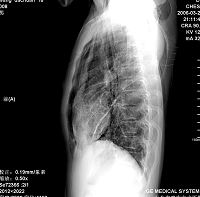

王某某,男,16岁,既往无经常咳嗽、咳痰、胸闷、发热史,活动与同龄儿童相似,三月前突感胸、颈前痛、无喘憋,查体胸骨上皮下气肿,双肺呼吸音对称。胸部dr及ct示纵隔气肿,双肺囊肿。近两月反复出现胸痛、喘憋,无发热、黄痰及痰血,呼吸音减低,胸部dr示双侧自发性(张力性)气胸,胸腔闭式引流治愈。频繁发作,左侧引流两次,右侧引流三次。

1.诊断考虑先天性肺囊肿(囊性肺),自发性、张力性气胸,鉴别支气管扩张,先天性囊性腺瘤样畸形等

从上述x线片、ct片看,先考虑先天性肺囊肿(囊性肺),伴气胸、纵隔积气、皮下积气;先天性囊性腺瘤样畸形,一般中叶很少累及.

先考虑先天性肺囊肿(囊性肺),伴气胸、纵隔积气、皮下积气,胸水.先天性囊性腺瘤样畸形